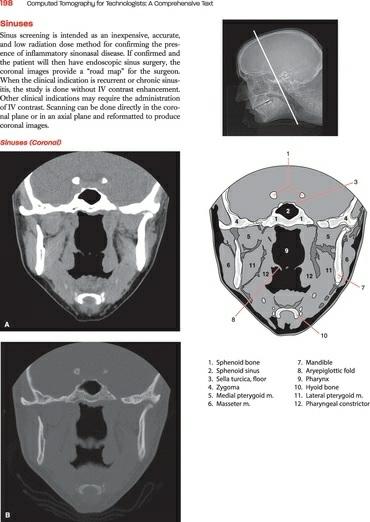

The ability to accurately identify cross-sectional anatomy is an important aspect of the technologist’s job and comprises a significant portion of the ARRT certification exam. The anatomy section included in this text is intended only as an introduction to cross-sectional anatomy; the images included should give the reader an idea of the level of anatomic detail with which the technologist is expected to become familiar. Many excellent texts currently exist that provide a full range of cross-sectional images, should the reader wish to continue their studies.

CT Cross-Sectional Slices accompanied by shaded diagrams and a reference image are featured in the Cross-Sectional Anatomy section of the book.